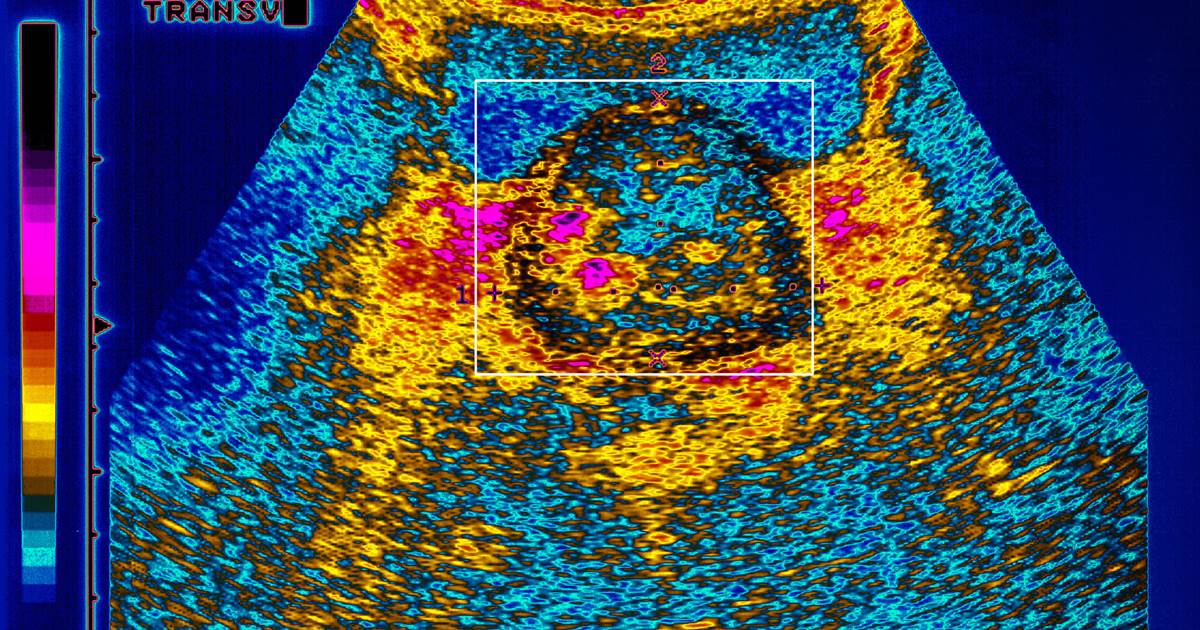

Black men are twice as likely to die of prostate cancer as white men. Government scientists said Tuesday that they are launching a study to try to discover why. The aim is to gather samples from 10,000 prostate cancer patients to see if genes, stress, segregation or other factors […]